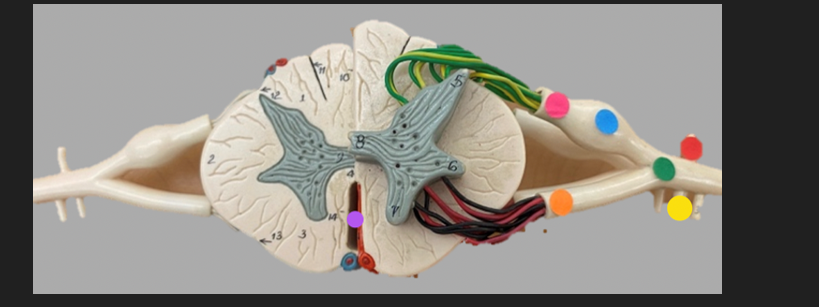

green dot

spinal nerve

orange dot

ventral root

pink dot

dorsal root

blue dot

dorsal root ganglion

red dot

dorsal ramus

yellow dot

ventral ramus

purple dot

anterior median fissure

red dot

posterior (dorsal) horn

purple dot

lateral horn

dark blue dot

anterior (ventral) horn

orange dot

dorsal column

yellow dot

lateral column

dark green

anterior column

line green and pink doit

gray commissure

light blue dot

posterior median sulcus